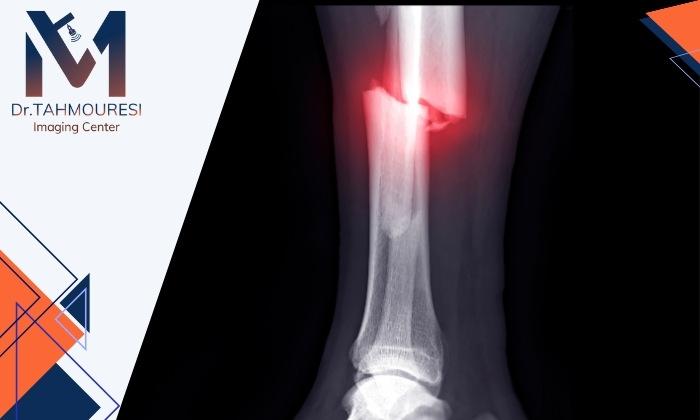

شکستگی استخوان همیشه با عکس ساده (رادیولوژی) مشخص نمیشود. رادیوگرافی در بیشتر موارد مخصوصاً در شکستگیهای واضح یا استخوانهای بزرگ (مانند بازو، ساق و ران) عملکرد خوبی دارد. اما در برخی انواع شکستگیها ممکن است تصویر واضحی در عکس دیده نشود.

بنابراین رادیولوژی روش مهمی برای تشخیص اولیهی شکستگی استخوان است اما همیشه کافی نیست. اگر علائم بالینی مثل درد، تورم و ناتوانی در حرکت وجود داشته باشد و عکس طبیعی به نظر برسد باید بررسیهای تکمیلی انجام شود تا شکستگی پنهان (Hidden Fracture) نادیده نماند. شایان ذکر است اگر قصد انجام رادیولوژی در فردیس کرج را دارید میتوانید به مرکز تصویربرداری مجهز دکتر موسی طهمورسی مراجعه کنید.